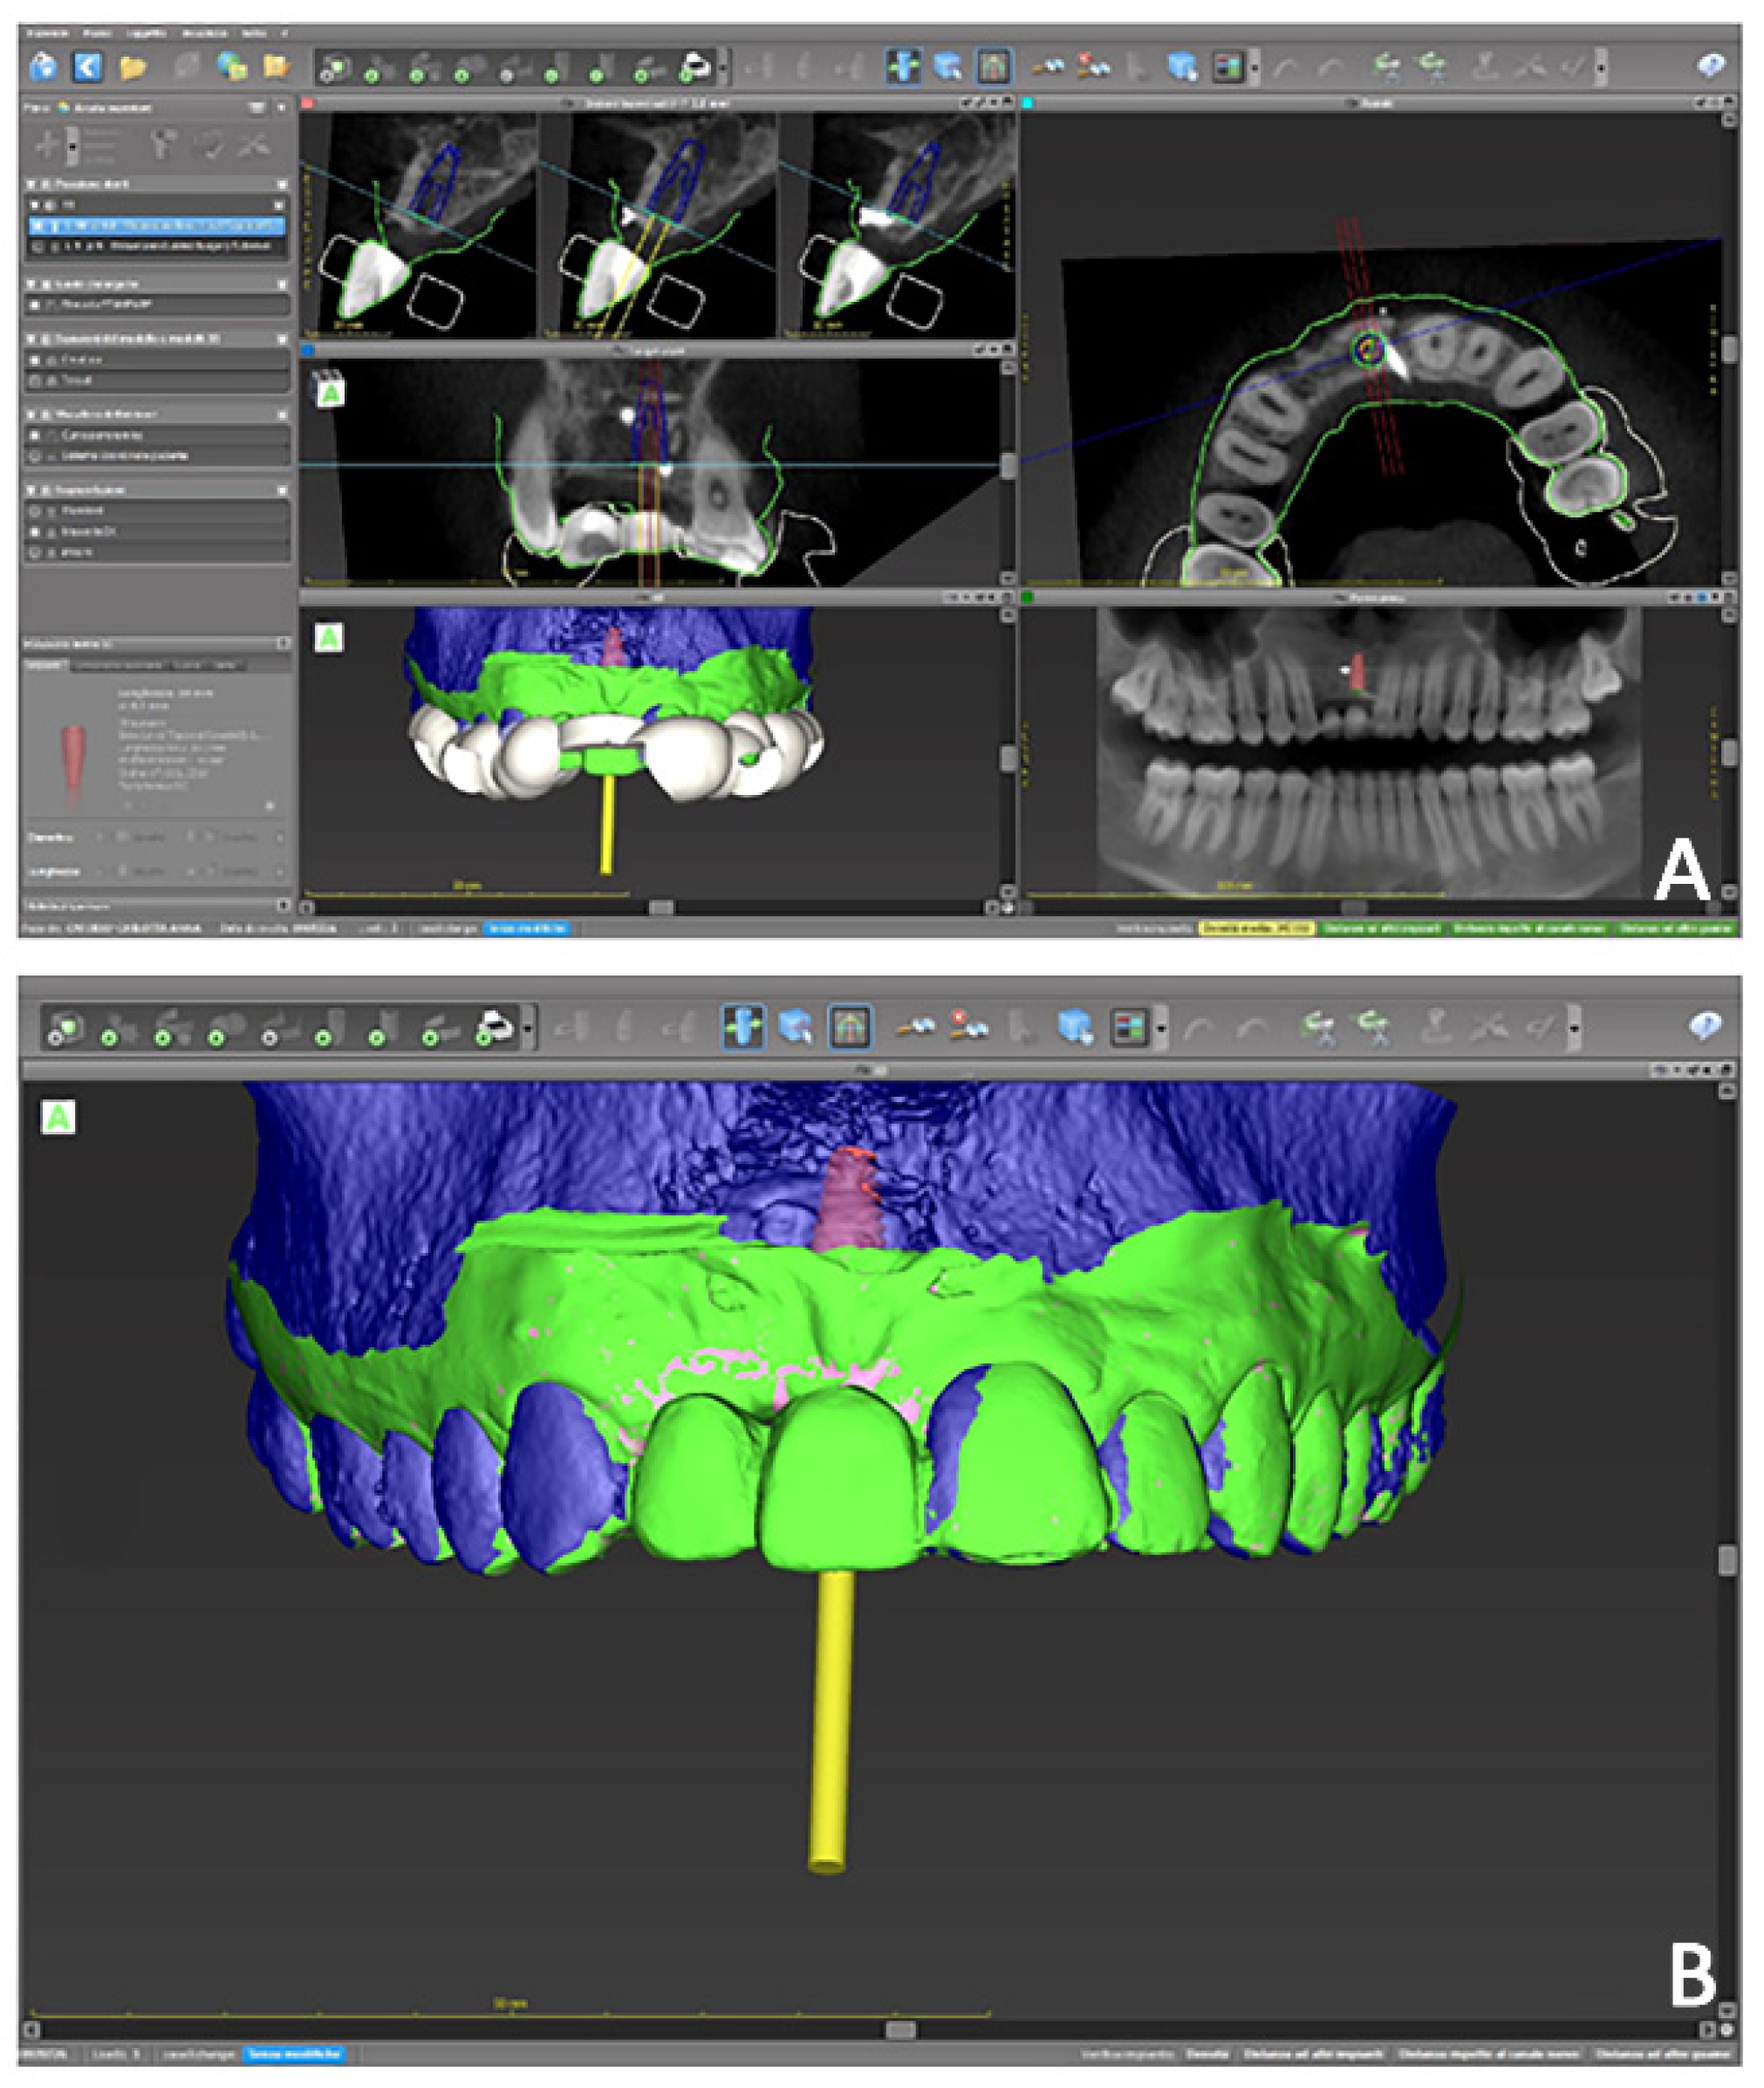

• Prosthetically guided implant planning. After removing the provisional prosthesis, an intra-oral scan was recorded, and the lab technician was asked to produce a virtual wax-up of the ideal position of the teeth. A Cone-Beam Computed Tomography (CBCT) was performed, and the 3D rendered model of the maxilla was registered with the intra-oral scan using the implant planning software Co-Diagnostix (Straumann, Montreal, Canada) (Figure 9). The software was used to plan the implant’s ideal position and design a surgery guide. Figure 10 shows the clinical procedure of the guided implant surgery. Once the osseointegration occurred, an intra-oral scan was performed to register the position of the implant and the surrounding soft tissues with the healing abutment in place (Figure 11A,B).

Figure 9. Case 2. Digital planning of implant placement and design of surgery guide. (A) Multiple 2D and 3D view; (B) 3D prosthetically guided implant surgery simulation.